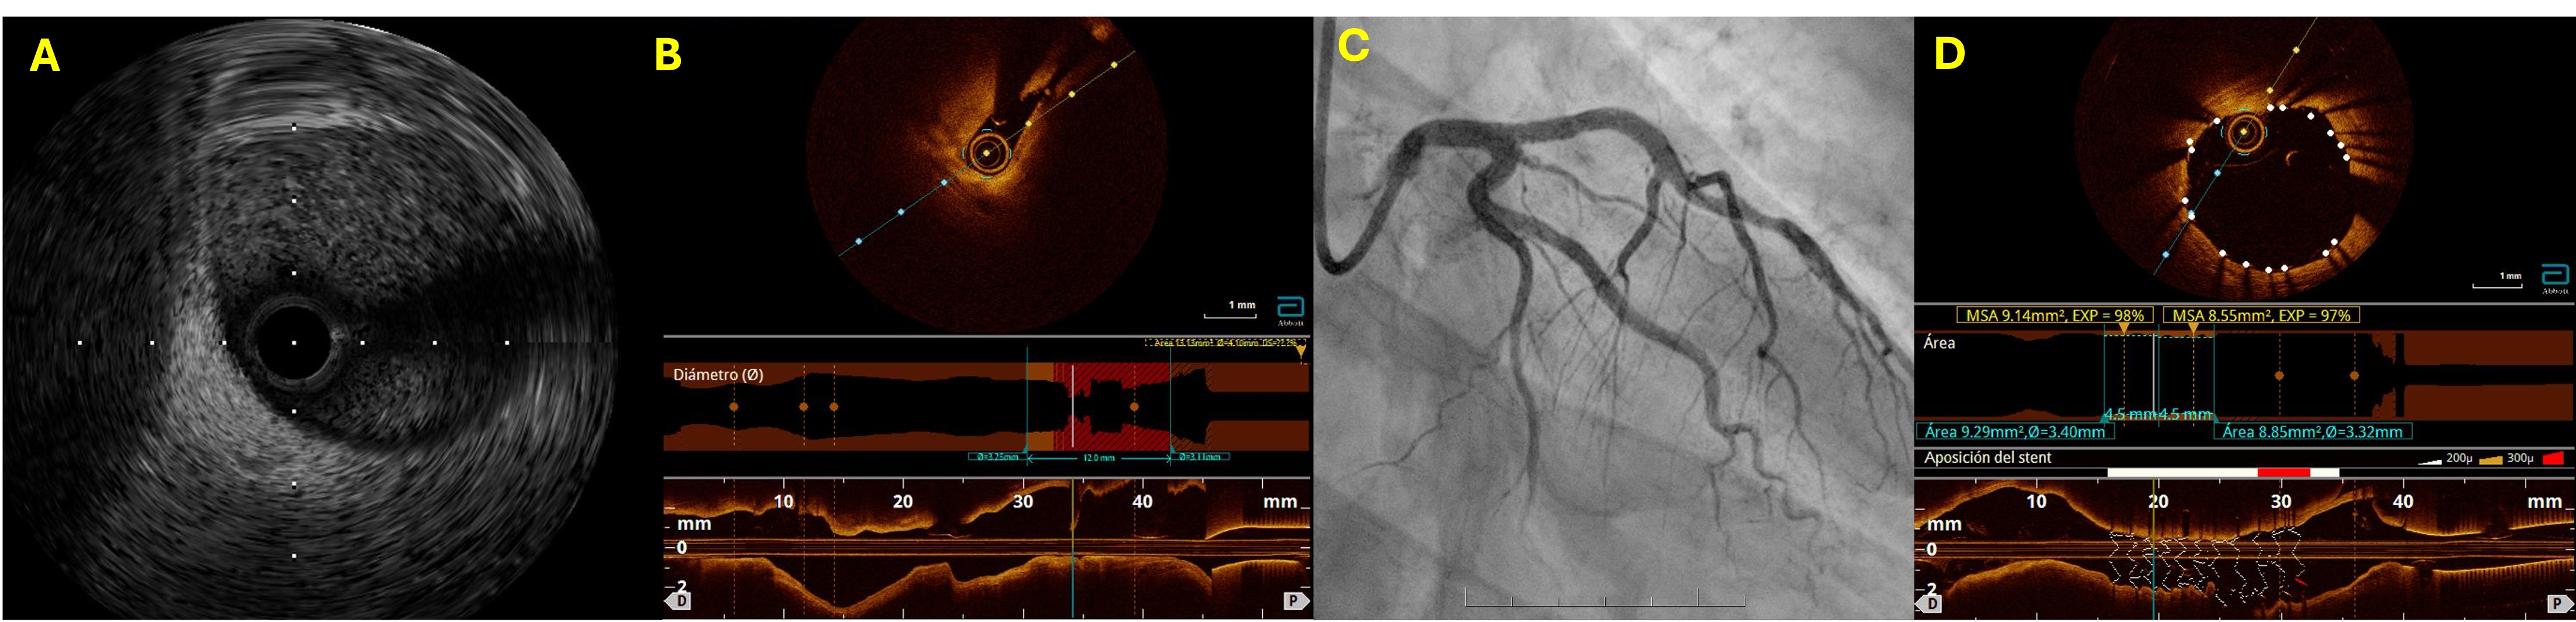

A: IVUS demonstrated mild eccentric plaque (MLA 6.9 mm²) without thrombus or dissection, B: OCT identified a short flap and entry tear ( <1 mm) at the LAD ostium, compatible with coronary plaque microdissection, causing focal stenosis, C,D: PCI with drug-eluting stent implantation was performed with optimal OCT-confirmed result.